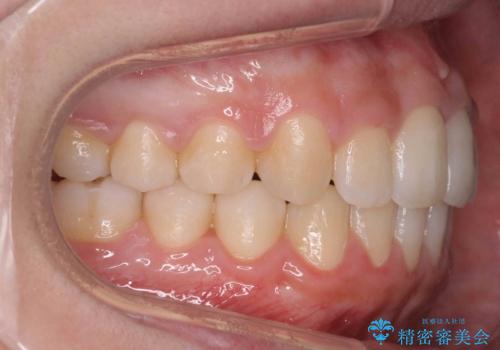

歯を抜かない矯正 出っ歯を抜かずに大きく下げることは可能です。

- 出っ歯を主訴に来院。

上の歯を全体に大きく後ろに下げる治療計画を立てました。

後ろに下げるために、親知らずは抜歯しています。

後ろに下げるために、ワイヤー矯正の前にカリエールという装置を使用しました。